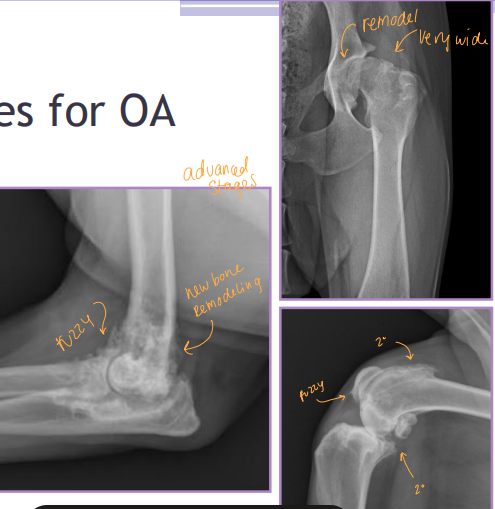

Radiography (#1): Evaluates subchondral bone, cartilage lesions, synovium

Cons: Not sensitive in early stages, Limited soft tissue evaluation, Poor correlation with clinical signs: do not tx the xray

Rads: Bone shape, remodeling, osteophytosis(neck), enthesiophytosis (Morgan’s line), laxity

Do not treat the radiograph!

Dt: Lateral, AP, flexed, Crlat-oblique

Rads: Osteophytes(back of elbow), Effusion, Subtrochlear sclerosis, Joint incongruity